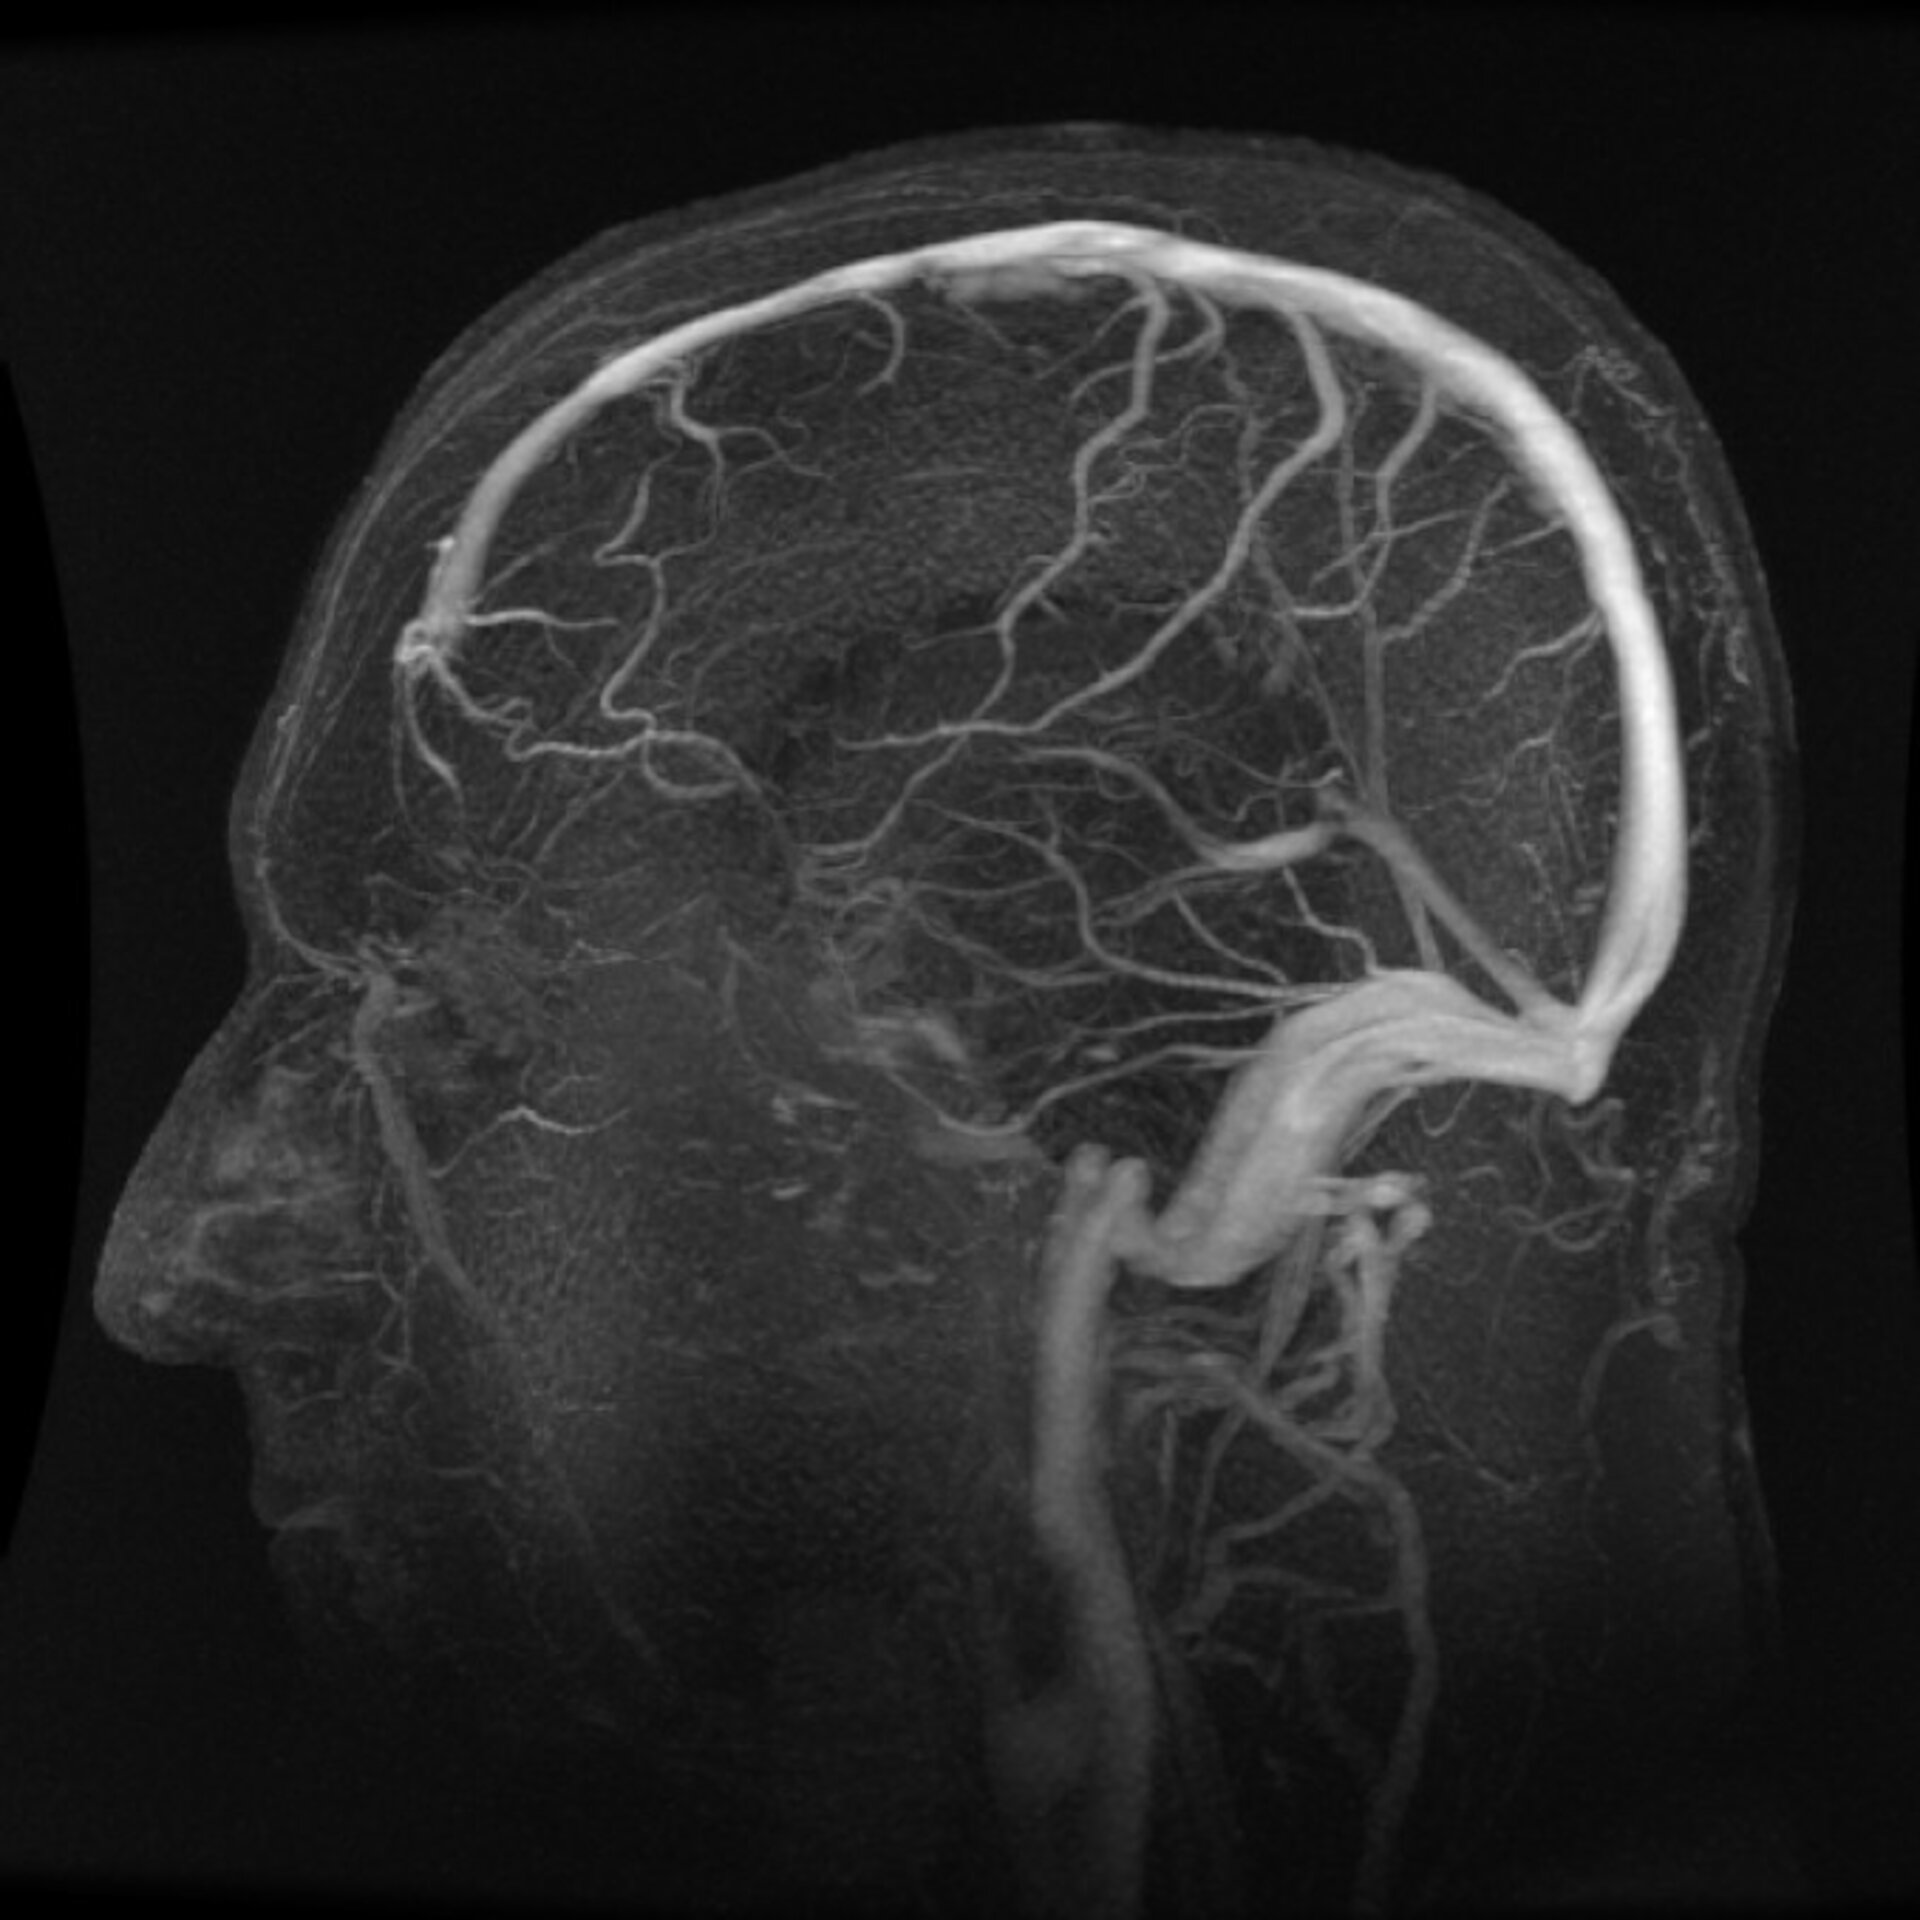

La investigación espacial ha desarrollado un nuevo método para medir la presión dentro del cráneo utilizando sencillas ondas de sonido provenientes de unos auriculares. El dispositivo es un efectivo sistema de aviso temprano para pacientes en fase de recuperación que hayan sufrido algún daño en la cabeza o algún tipo de cirugía cerebral.

Al igual que con la presión de la sangre, nuestro cuerpo controla la presión del fluido que rodea al cerebro para amortiguarlo con respecto al cráneo.

Monitorizar la ‘presión intracraneal’ no es sencillo – existen muchas técnicas, pero son complejas, invasivas y requieren de operación.

En 1994, Paul Avan, de la Universidad de Auvergne, en Clermont-Ferrand (Francia), investigó la posibilidad de medir los cambios en la presión mirando en una zona conectada que no fuera la zona intracraneal: la presión del oído interno.

Desarrolló un dispositivo que emite sonidos hacia el interior del oído y registra el eco con el fin de calcular el cambio en la presión que se da entre lecturas.